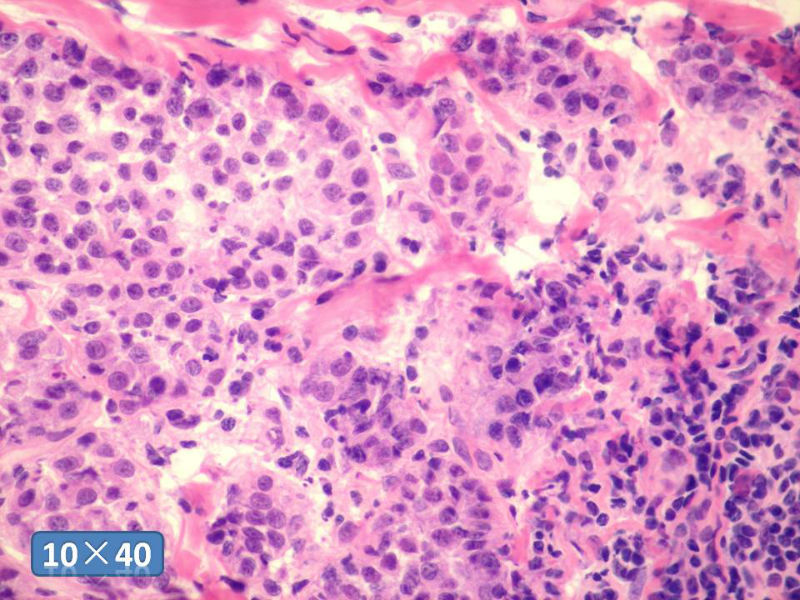

女性,50岁,乳腺肿物,冰冻切片(图1-25)

HE